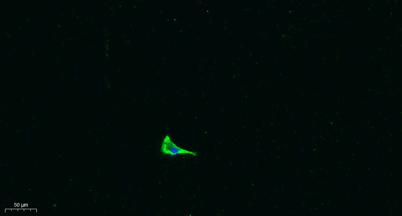

WB IF

Recomended Dilution WB 1:500-2000 IF 1:100-300 ELISA 1:5000-20000 Not yet tested in other applications.